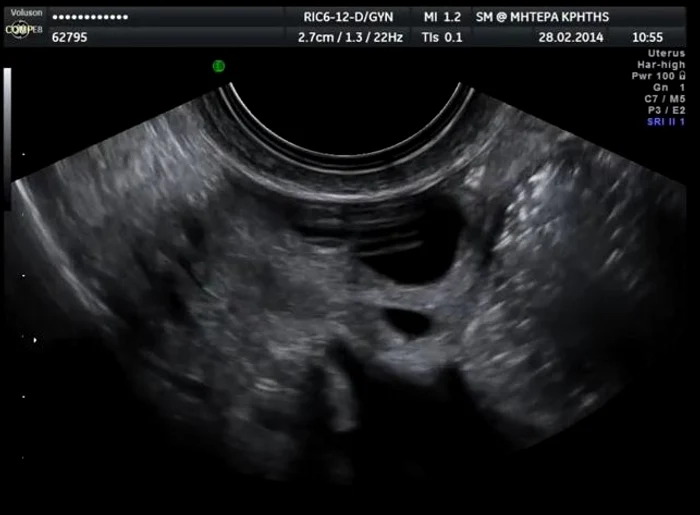

În cele din urmă, aceștia au descoperit că avea o tumoră de dimensiunile unei mingi de fotbal, specifică unui tip de cancer ovarian foarte rar, care apare, de obicei, la femeile cu vârsta cuprinsă între 15 și 20 de ani.